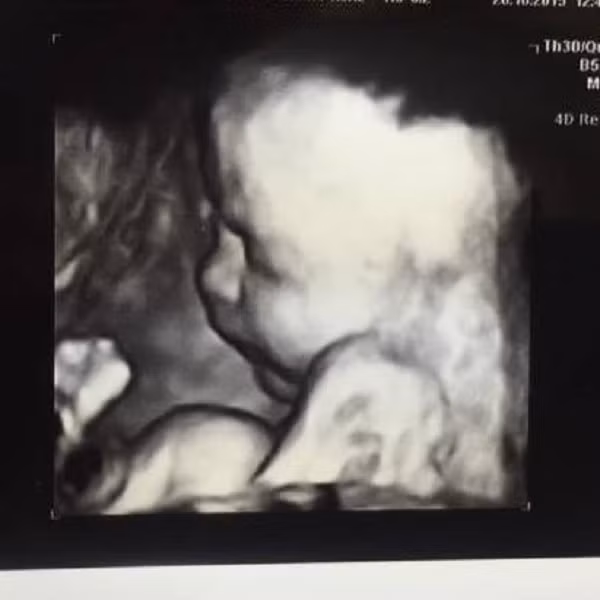

| Thai nhi khi đang ở trong bụng bà ngoại. |

Bà Tracy đã được cấy ghép phôi thai của con gái mình. Quá trình mang thai bà đều được chăm sóc và theo dõi y tế đặc biệt. Dù đã trải qua 7 năm mãn kinh nhưng sức khỏe của bà vẫn rất xuất sắc.